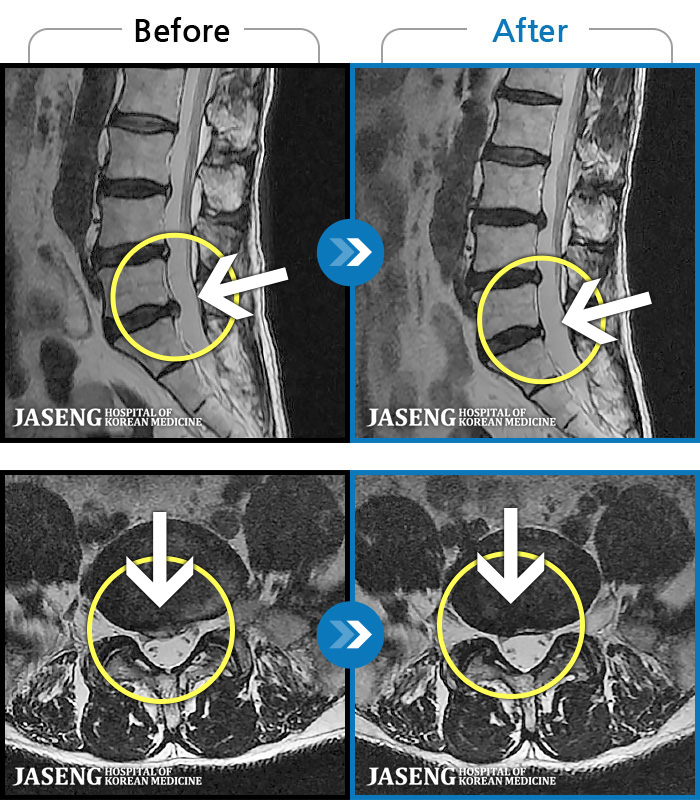

MRI ũ ʸ Ȯϼ.

| [ؿ] 24.10.10~25.04.23

ȯںп Ǹ  ǿ ԿǾ, ο ġ ۿ  Ƿ ġḦ Ͻñ ٶϴ.   | ||||